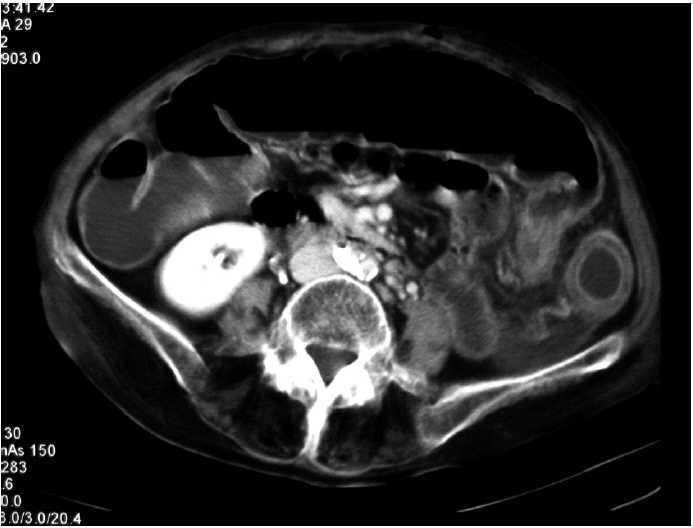

Paciente de 72 años con factores de riesgo cardiovascular, intervenida de urgencia por perforación intestinal y peritonitis, secundaria a obstrucción intestinal por adherencias. Se realiza resección intestinal y adherensiólisis. Durante el postoperatorio se mantiene antibioterapia de amplio espectro por vía intravenosa; presenta deposiciones diarreicas y en el 14.o día, dolor y distensión abdominal. La tomografía computarizada de abdomen (fig. 1 y 2) es compatible con colitis isquémica de colon izquierdo y recto, con neumatosis intestinal. Analíticamente, no presentaba alteraciones indicativas de isquemia intestinal, salvo leucocitosis en ascenso. Ante la sospecha de colitis seudomembranosa, se solicita detección de toxina de Clostridium difficile en heces, que es positiva; se resolvió el cuadro con metronidazol por vía oral.

Fig. 1.